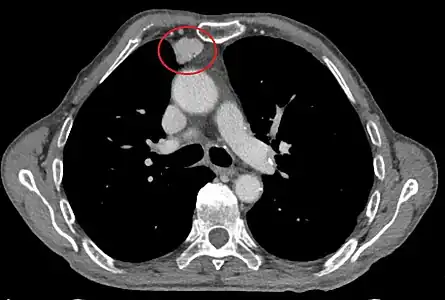

Scanner thoracique

Le scanner thoracique est plus précis que la radiographie thoracique dans le diagnostic des thymomes, en raison d'une plus grande sensibilité envers les masses médiastinales. L'injection de produit de contraste iodé n'est pas forcément nécessaire, mais permet de préciser les rapports du thymome avec les structures vasculaires. Ceci permet à la fois la stadification et de préciser la stratégie chirurgicale lorsqu'elle est envisagée[28].

Les thymomes se présentent comme une masse bien définie du médiastin antérieur, proche du péricarde et dans un plan plus antérieur que les gros vaisseaux intrathoraciques (aorte ascendante et sa crosse, artère pulmonaire, veine cave supérieure). La masse peut être sphérique ou lobulée, mais présente un aspect homogène (plus rarement kystique) qui se réhausse après injection et peut contenir des calcifications[29].

Les critères scanographiques d'envahissement local doivent être recherchés car ils guideront le traitement. D'autre part, l'envahissement scanographique est corrélé au pronostic[30]. L'absence d'un liseré graisseux entre la masse et les vaisseaux, notamment l'aorte et la veine cave supérieure, est un signe d'envahissement local. L'ascension d'une coupole diaphragmatique, comme en radiographie thoracique, est un signe d'envahissement du nerf phrénique[31].

L'irrégularité des contours de la tumeur, ainsi que la présence de calcifications, de nécrose ou d'hémorragie intratumorale sont des signes de mauvais pronostic corrélés à des tumeurs plus agressives[32].

Scanner injecté, en fenêtre médiastinale, montrant un carcinome thymique envahissant les structures médiastinales :

1 : tumeur hétérogène, aux contours irréguliers, présentant des plages hémorragiques ;

2 : veine cave supérieure ;

3 : tronc artériel brachiocéphalique ;

4 : artères sous-clavière gauche et carotide commune gauche ;

5 : crosse de l'aorte ;

6 : sternum.- Scanner en fenêtre parenchymateuse, montrant un carcinome thymique envahissant les poumons (avec des lésions d'emphysème) au contact des deux poumons (1 : poumon droit ; 2 : poumon gauche) ;

flèches noires : zones suspectes d'envahissement.